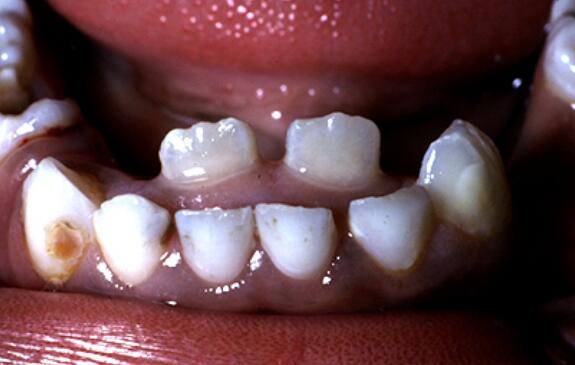

这是个俗语,通常是指恒牙长出来后,乳牙还不脱落,形成前后两排牙齿的表现,如下图所示。

图片来自参考文献[1]

大家能看出来哪些是恒牙吗?哈哈,当然是里面那两颗大的下切牙,从数量也能看出,在换牙时,乳牙数量肯定是比恒牙多的。

对于这种双排牙,最常见的是下切牙,也就是上面图片中所示的。